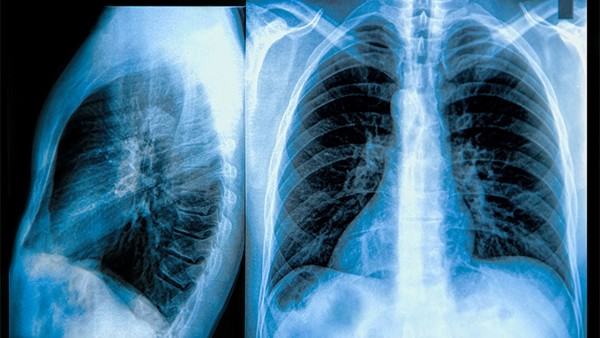

肺炎是一种常见且严重的呼吸道疾病,严重的肺炎病例可能会导致死亡。对于这种疾病,预防比治疗更为重要。在预防肺炎方面,疫苗是一种非常有效的措施,可以帮助人们降低患肺炎的风险,特别是对于易感人群如老年人、儿童和免疫系统较弱的个体来说尤为重要。 目前,针对不同类型的肺炎病原体,有多种疫苗可供预防使用。以下是一些常见的预防肺炎的疫苗: 1. 肺炎球菌疫苗:肺炎球菌是导致肺炎的主要病原体之一。目前市场上有23价肺炎球菌多糖疫苗(PPSV23)和13价肺炎球菌蛋白多糖疫苗(PCV13)可供使用。这些疫苗可以帮助预防由肺炎球菌引起的肺炎以及其他感染症。 2. 流感疫苗:流感病毒感染可能导致并发肺炎,因此定期接种流感疫苗可以减少患肺炎的风险,尤其是对于老年人、患有基础疾病的人群来说尤为必要。 3. 百日咳疫苗:百日咳是一种由百日咳杆菌引起的传染病,严重情况下可引发细菌性肺炎。接种百日咳疫苗可以有效预防百日咳引发的并发症,包括肺炎。 4. 流行性感冒疫苗:流行性感冒是由流感病毒引起的呼吸道感染疾病,严重情况下可引发病毒性肺炎。及时接种流感疫苗有助于减少患肺炎等并发症的风险。 总的来说,接种肺炎相关疫苗是预防肺炎的有效手段之一。在选择接种疫苗时,建议咨询医疗专业人员,根据个人实际情况和建议制定合适的疫苗接种计划。除了疫苗接种外,保持良好的个人卫生习惯、避免接触患者和改善免疫系统等也是预防肺炎的重要措施。希望大家能够重视肺炎的预防工作,保障自身和家人的健康。